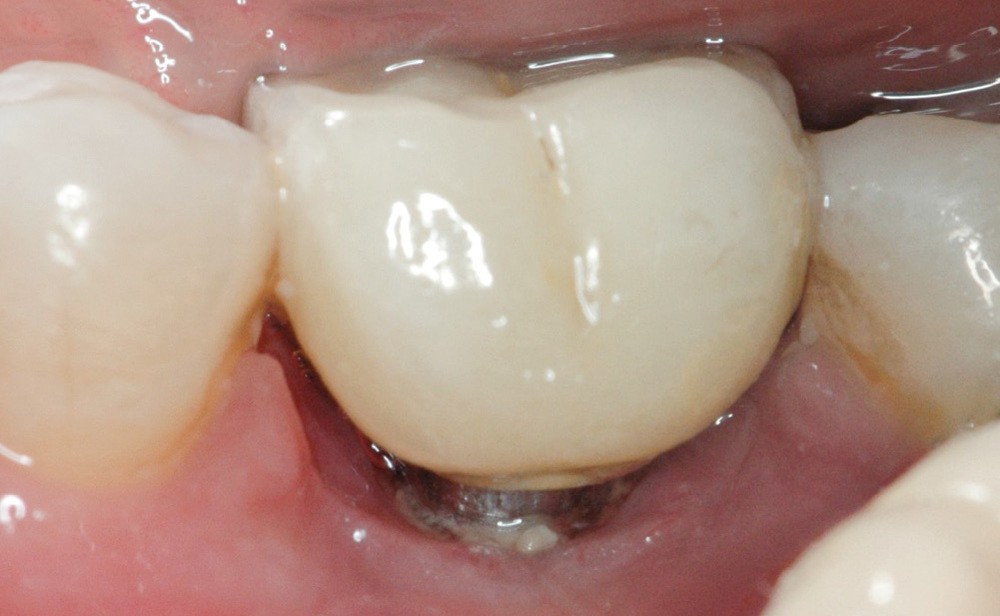

- Péri-implantite diagnostiquée en 2021

Chez ce patient, le traitement de la péri-implantite a comporté une chirurgie associant décontamination électrolytique de la surface implantaire, régénération osseuse guidée et enfouissement de l’implant. Le résultat à 2 ans est très moyen au vu du pourcentage de régénération osseuse obtenu. Comment peut-on prévoir un tel résultat alors que l’on a suivi les recommandations à la lettre, que l’on a utilisé les dernières technologies de décontamination, que l’on y a mis tous les moyens, que le patient est en bonne santé générale et qu’il vient en plus régulièrement aux séances de thérapeutique de soutien ? Le succès du traitement des péri-implantites n’est pas simple à obtenir, surtout quand un élément clé est compromis… la maintenance personnelle ! En effet le succès n’est possible que si le contrôle de plaque quotidien est optimal et, ici, ça n’était pas le cas. Le patient se brossait certes les dents, mais ne passait pas quotidiennement les brossettes, ce qui…